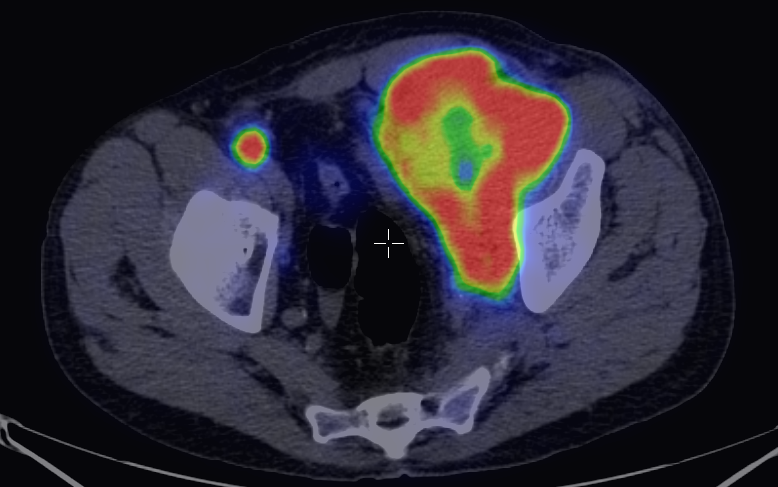

The greatest precision of image registration is achievable if the patient experiences minimal motion differences (the patient lies in the same position and imaging takes place almost at the same time) during both examinations. These requirements are met in hybrid imaging methods, with the implementation of the so called hardware registration. PET-CT, SPECT-CT or the newly emerging PET-MR examinations are all able to utilize hardware registration. The integrated PET/SPECT-CT method represents the latest technical developments of both PET and CT scanners, combined in one machine. It is capable to represent structural and metabolic information simultaneously and identically. The machine’s PET/SPECT and CT components are aligned along the common axial axis, and as the patient table moves along their longitudinal axis, the two examinations are carried out only minutes apart from each other, minimizing any movement or change in the patient’s position. During evaluation the identical slices of CT and PET can be matched with each other and they can be analyzed independently or represented in a fusion image. (Figure 1.)

1. Fusion images; FDG PET-CT, transversal and coronal planes. The dominance of certain components (transparency) can be constantly adjusted on the fused image.

Another advantage of hybrid imaging is that CT can be used for the attenuation correction (AC) of the PET images. Photons arriving from deeper lying tissues have a smaller chance of reaching the detector, due to greater scattering and absorption. The decrease in signal intensity is directly proportional with the local tissue densities. Thus, the activity-maps detected by PET and SPECT cameras do not represent real tissue dependent radiopharmaceutical distributions. Real activity distribution maps are only detectable with the knowledge of tissue densities that are calculated from the attenuation corrected maps, registered during the CT examination. For anatomic localization and attenuation correction, it is sufficient to take a non-diagnostic quality, low-dose CT scan.